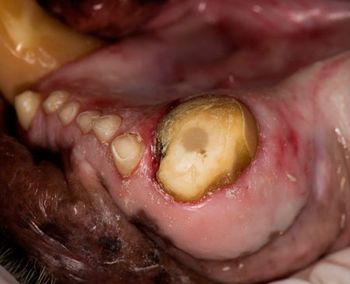

Weigh clinical, radiographic evidence as well as client expectations when approaching this preventable disease.

The degree of severity of periodontal disease relates to a single tooth; a patient may have teeth that have different stages of periodontal disease. Here is an outline of the American Veterinary Dental College-approved periodontal disease classifications.

Creating a dental treatment plan can be frustrating. As with other veterinary disciplines, dental diagnosis and care is one-third recognition of disease, one-third understanding anatomy and medical principles, and the last third performing needed care.